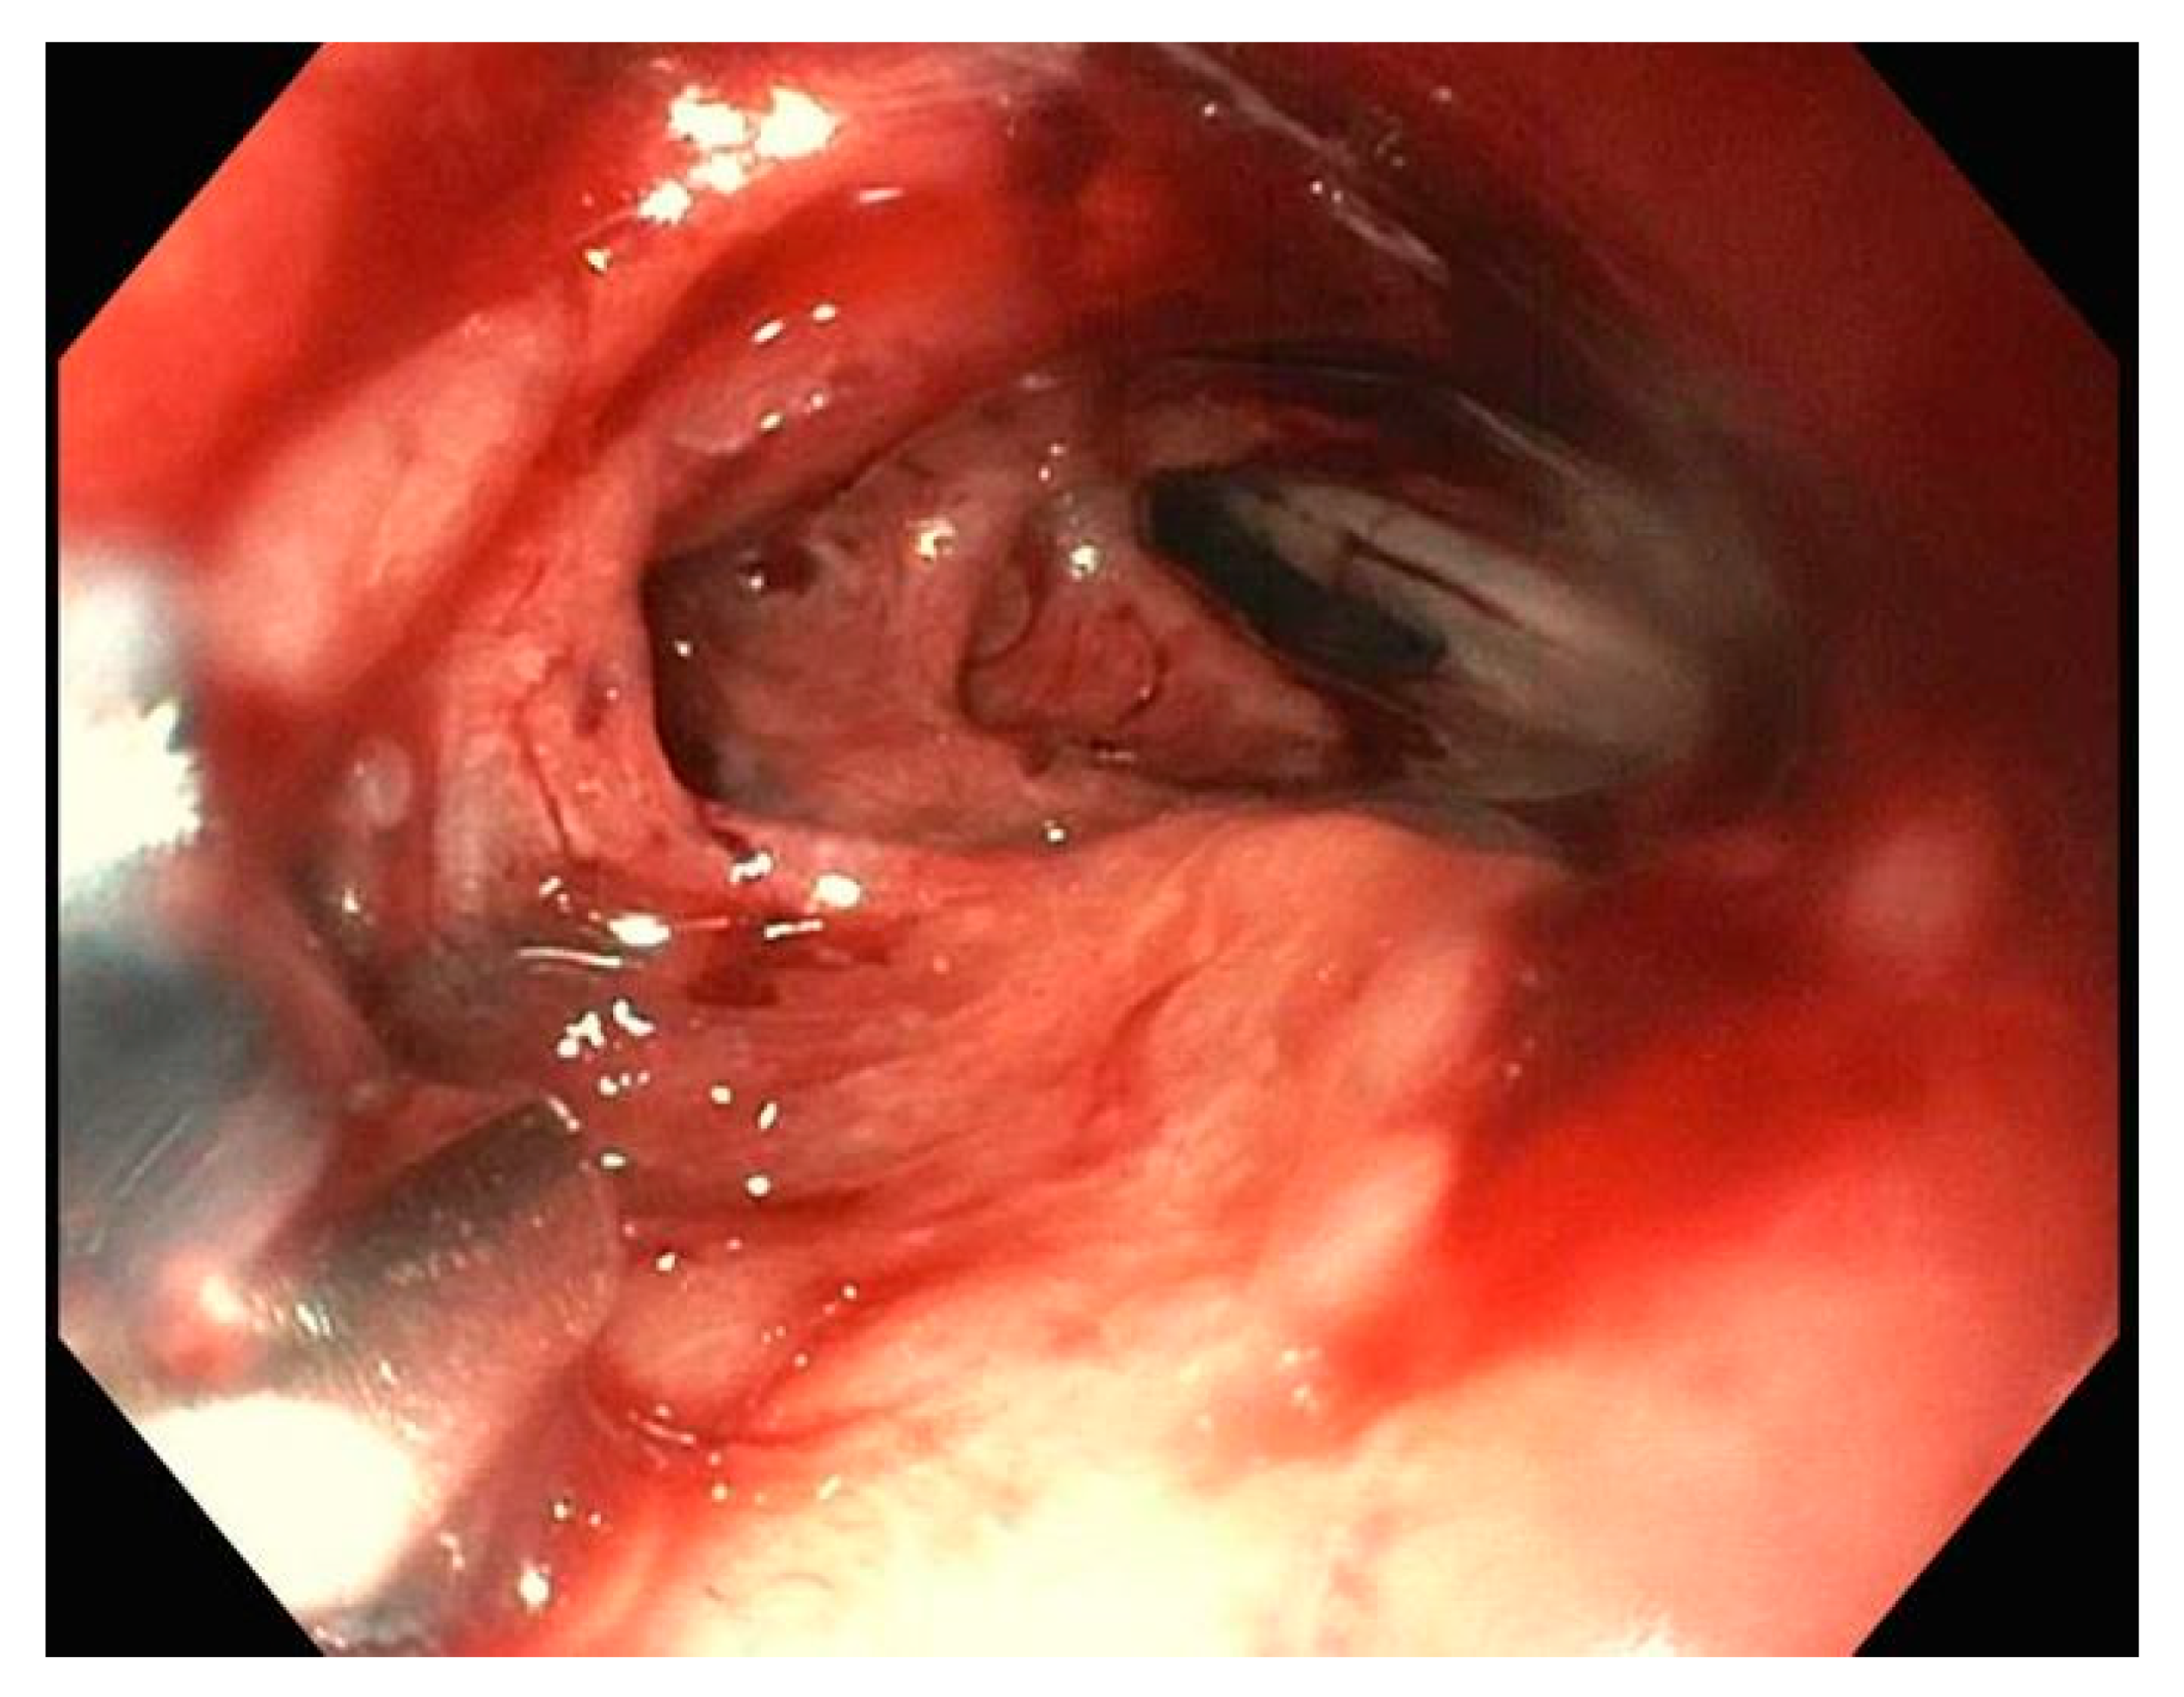

2. Endoclips